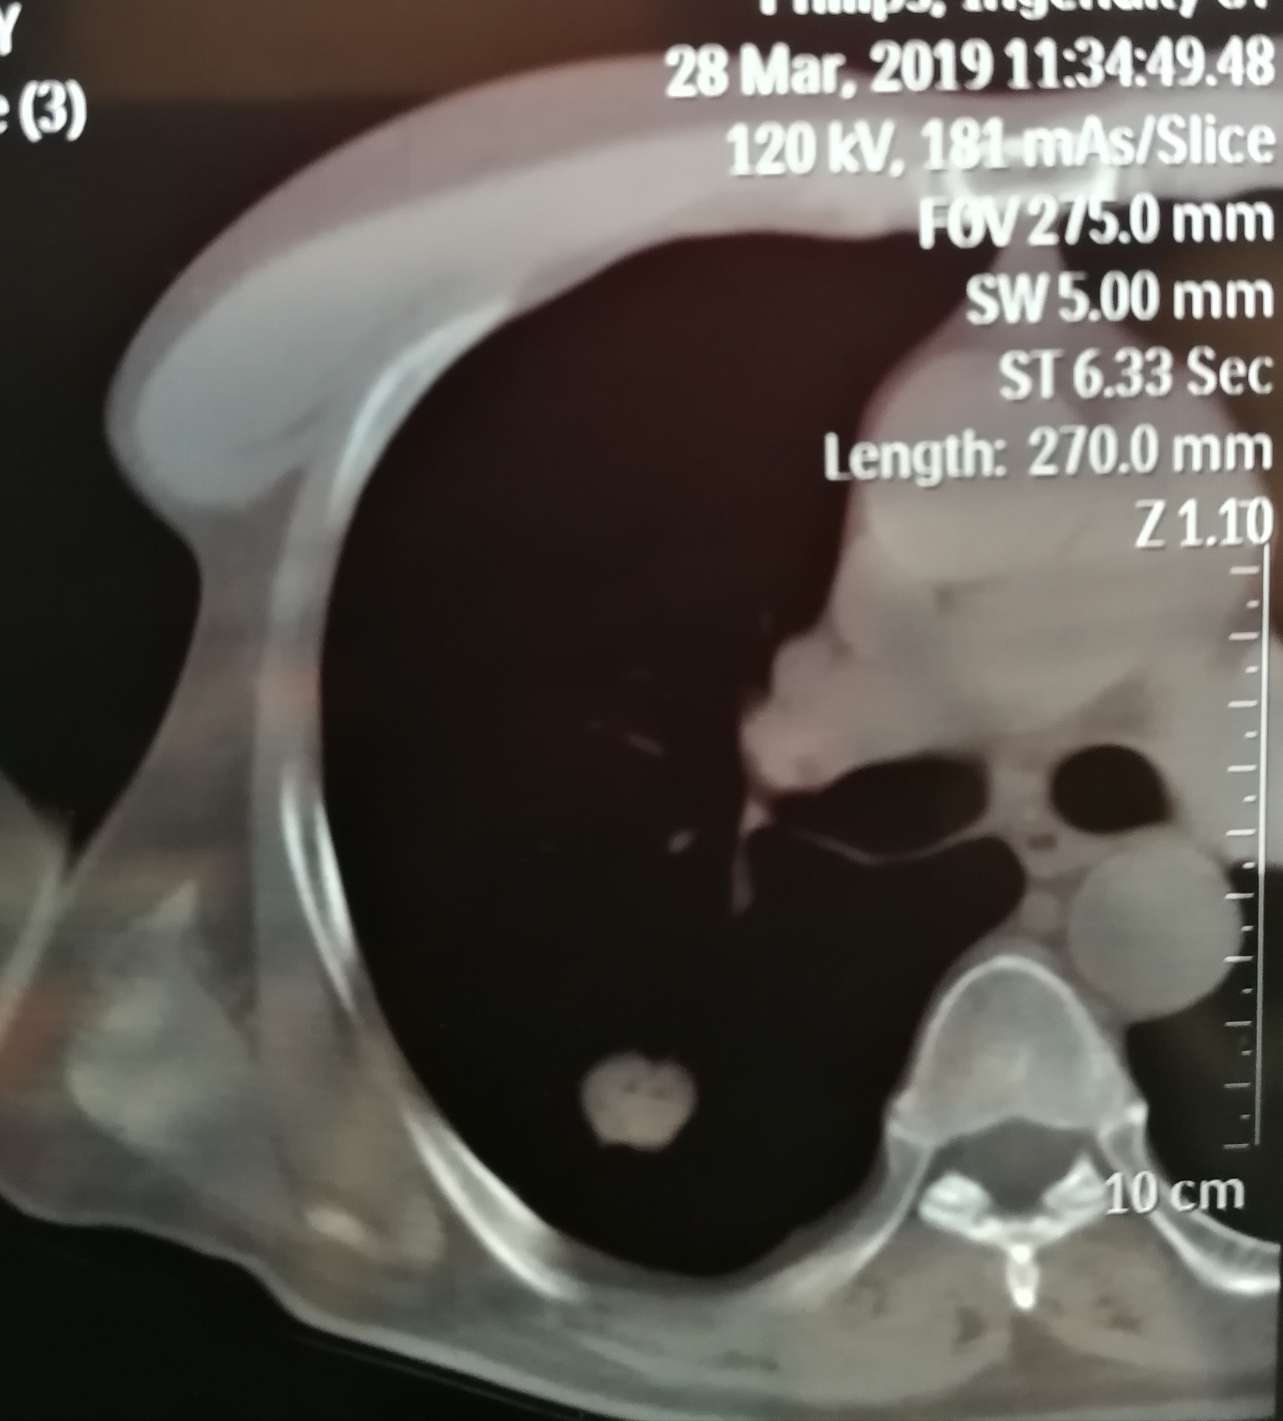

我父亲今年67岁,今年3月28日无任何症状下CT意外发现肺部占位病变。医生描述1.6*1.6cm结节,肺癌可能性较大。

随后又做了胸部增强CT,进一步确定肺部占位病变,大小1.6*1.7cm。